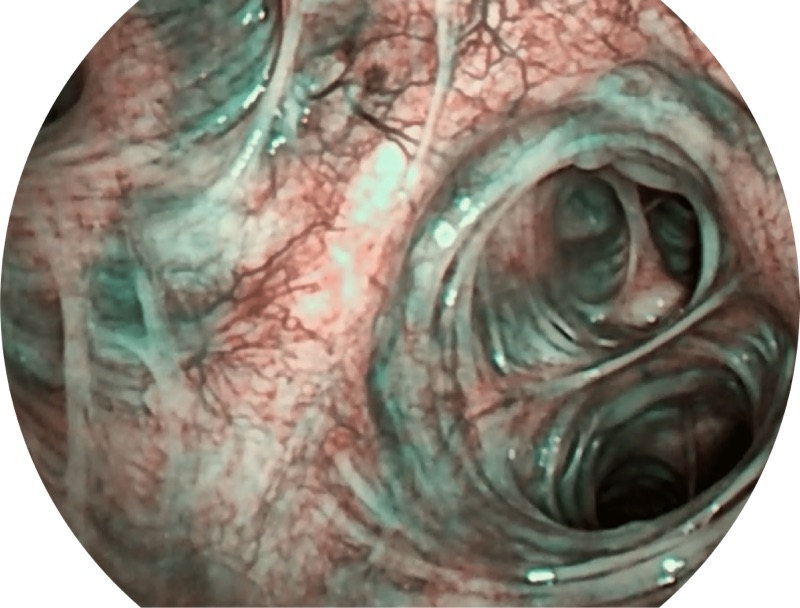

帮助医生更加清晰地观察气管表面病灶

VIST